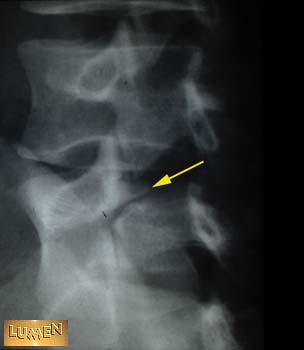

Where is the fracture?

Answer

Pars interarticularis.